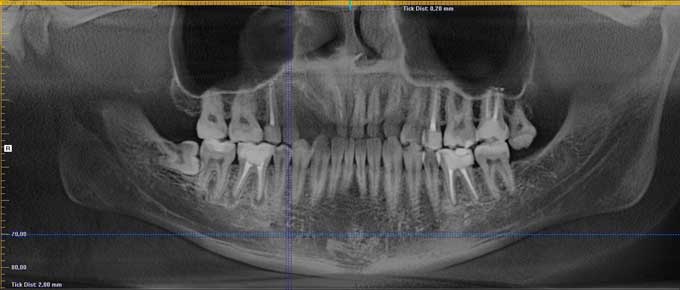

Правильный диагноз сможет поставить только стоматолог на основании сделанного рентгена. На снимке можно увидеть небольшой затемненный участок около корня зуба.

В больнице так же можно сделать радиовизиографию. Эта разновидность рентгеновского исследования с меньшим облучением. Результаты оценивают не на снимке, на экране монитора. По этой причине такое обследования часто называют цифровым.

Для постановки диагноза пациенту назначается рентгенография. Реже используют радиовитзиография – современный способ рентгенологического исследования, при котором пациент получает меньшую дозу облучения. Результаты исследования выводятся на монитор компьютера.